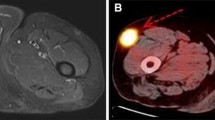

Observed sensitivity, specificity, and estimated posterior mean ROC curve—18F-FDG PET and 18F-FDG PET/CT. Each point in the scatterplot depicts the observed sensitivity and 1-specificity for one study. Color is used to indicate the study. The line depicts the estimated mean ROC curve obtained from meta-analysis. The vertical line represents the 99 % posterior predictive credible interval that is obtained for the Ahmed et al. [12] study when predicting sensitivity under the assumption of two malignant lesions

Observed sensitivity, specificity, and estimated posterior mean ROC curve of the observed results by modality—18F-FDG PET and 18F-FDG PET/CT. Each point in the scatterplot depicts the observed sensitivity and 1-specificity for one study. Color is used to indicate the modality used in the study. The line depicts the estimated mean ROC curve obtained from meta-analysis based on both modalities